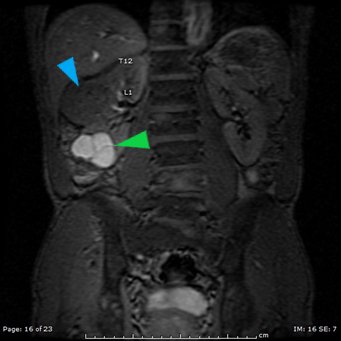

The MRI showed extensive spondylotic changes suggestive of malignancy (red arrows) with severe spinal canal stenosis at the lumbar spine L3-L4 (purple arrows) level contributing to clumping of cauda equina nerve roots and severe bilateral neuroforaminal narrowing with diffuse disc bulges abutting the exiting nerve roots at multiple levels. Findings also showed a hypo-attenuated tumor (blue arrow) and hyper-attenuated loculated tumor (green arrow) consistent with renal cell carcinoma (RCC).